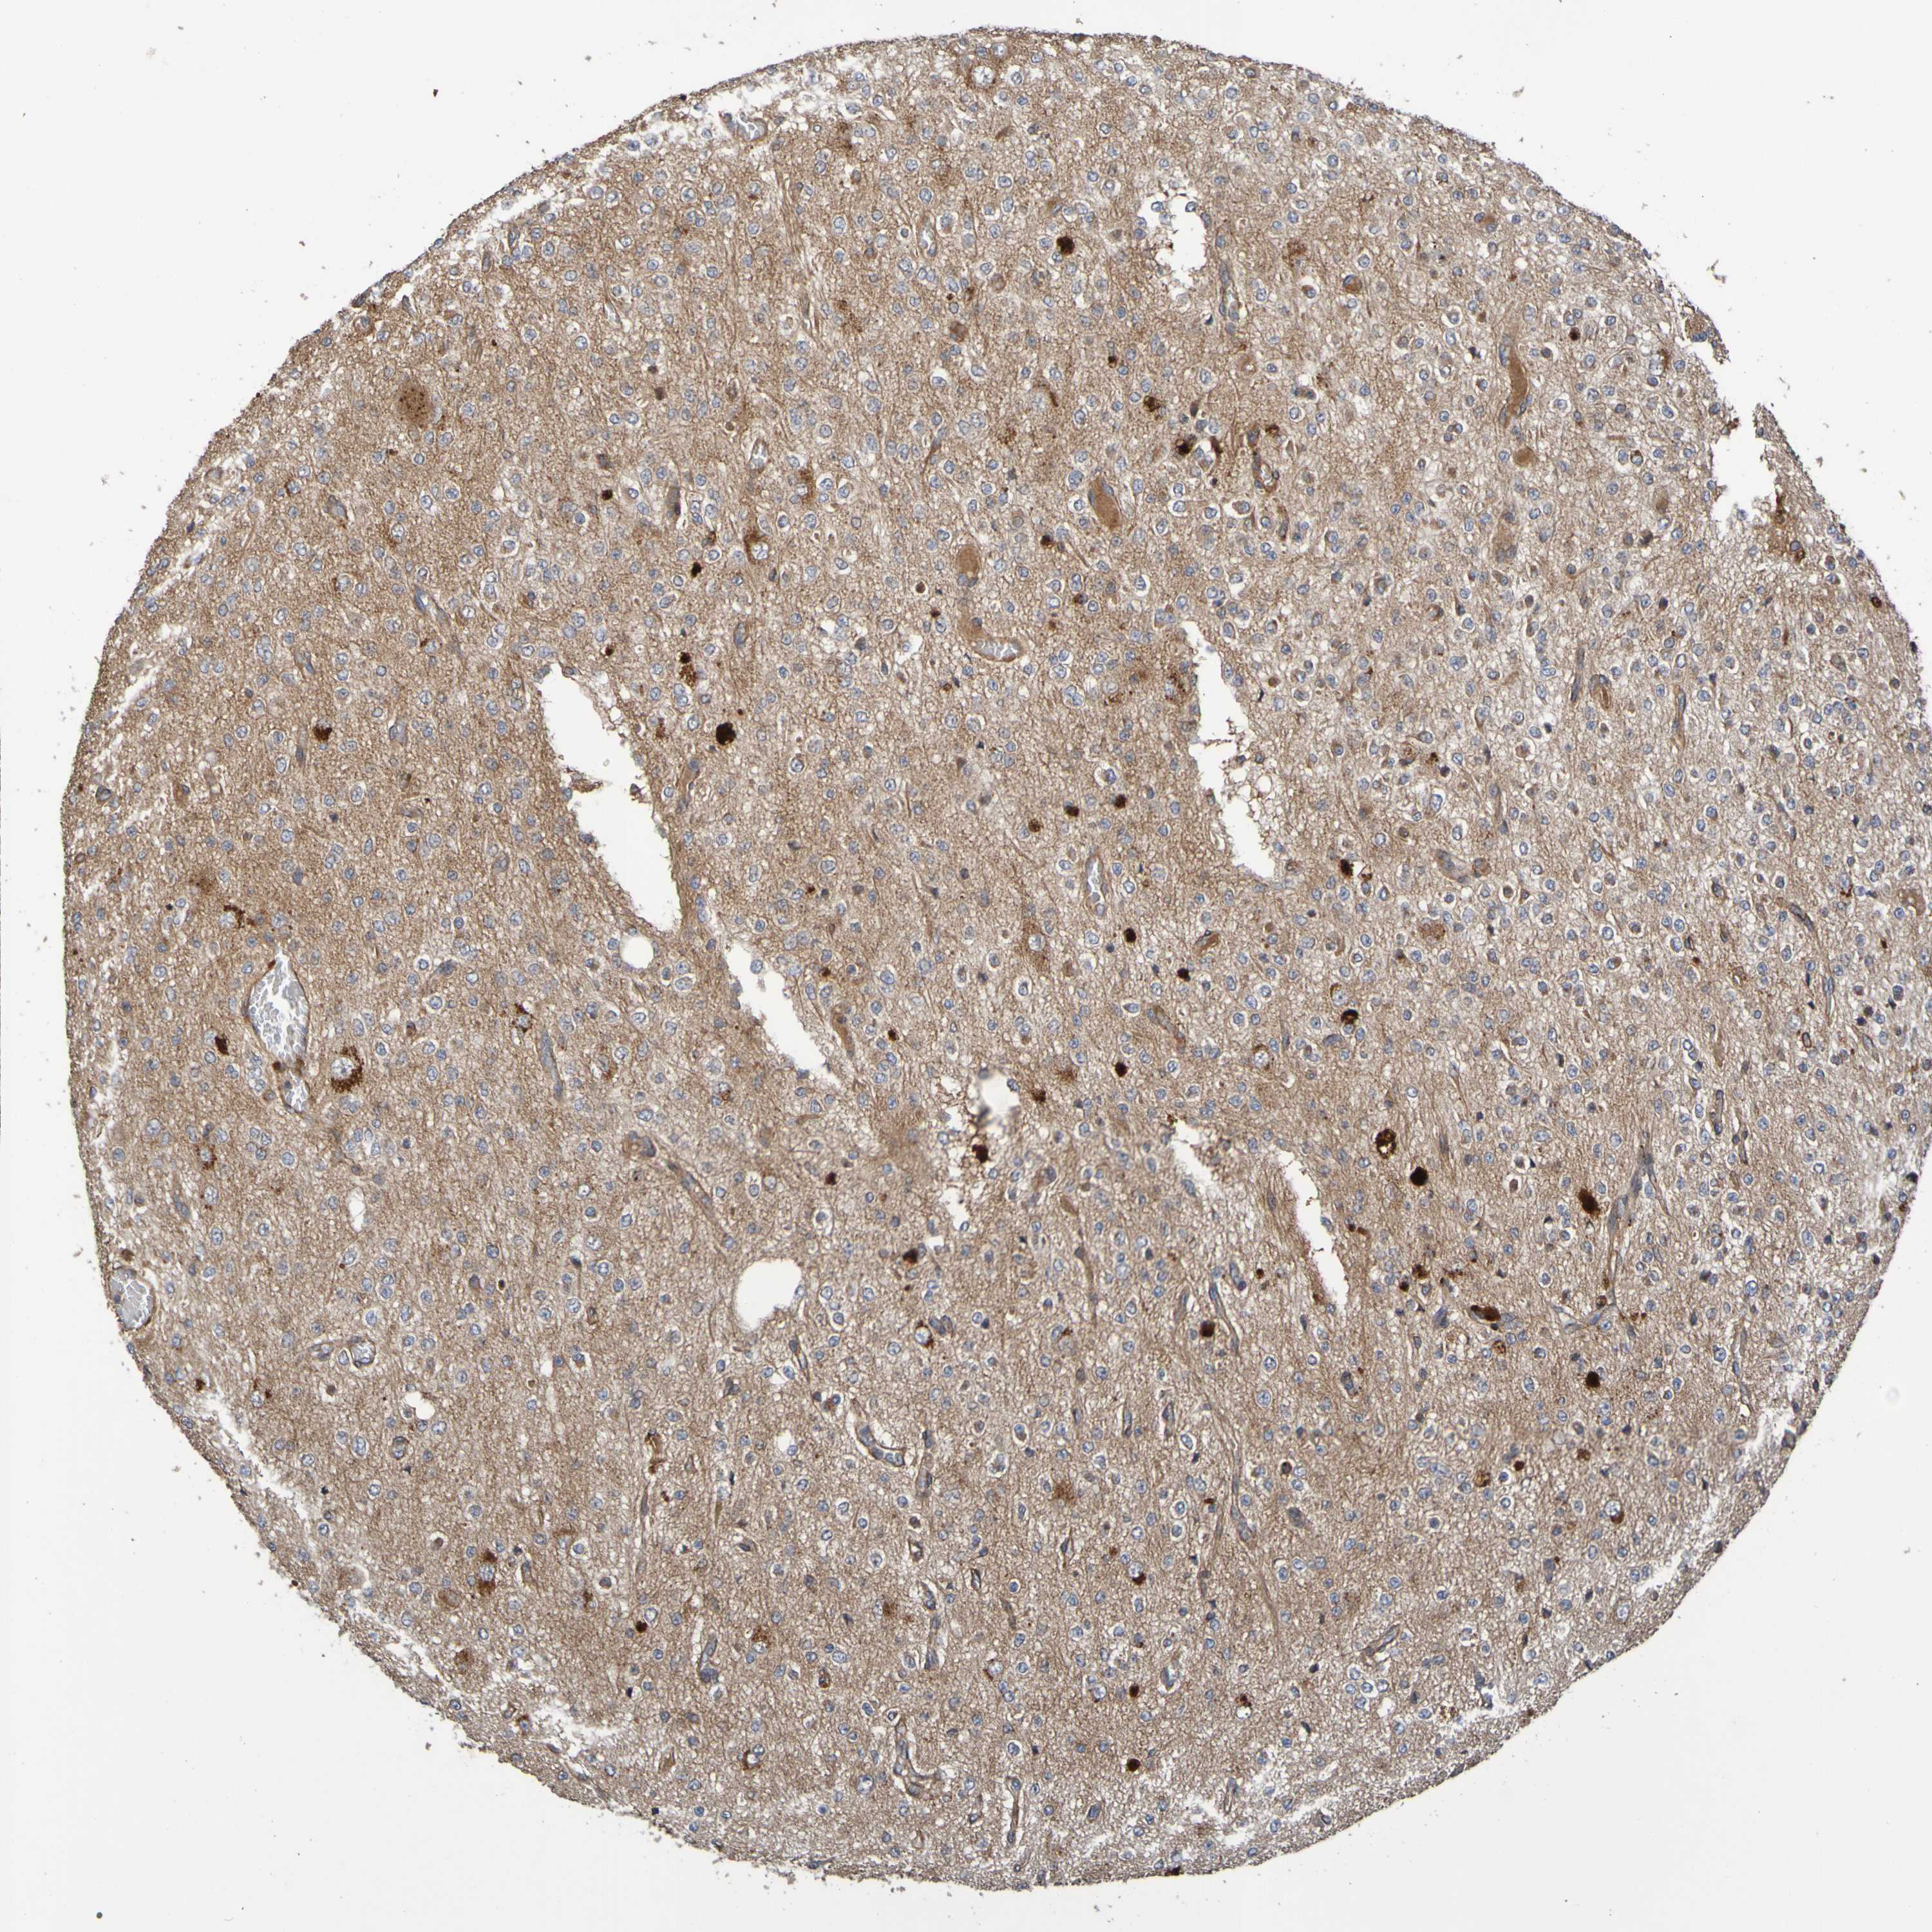

GLIOMA - Protein expressioni

A mouse-over function shows sample information and annotation data. Click on an image to view it in a full screen mode. Samples can be filtered based on level of antibody staining by selecting one or several of the following categories: high, medium, low and not detected. The assay and annotation is described here.

Note that samples used for immunohistochemistry by the Human Protein Atlas do not correspond to samples in the TCGA dataset.

Antibody stainingi

Antibody staining in the annotated cell types in the current human tissue is reported as not detected, low, medium, or high, based on conventional immunohistochemistry profiling in selected tissues. This score is based on the combination of the staining intensity and fraction of stained cells.

Each image is clickable and will lead to virtual microscopy that enables deeper exploration of all samples and also displays staining intensity scores, fraction scores and subcellular localization as well as patient and tissue information for each sample.

Antibody CAB010911

Staining

High

Medium

Low

Not detected

Intensity

Strong

Moderate

Weak

Negative

Quantity

>75%

75%-25%

<25%

None

Location

Nuclear

Cytoplasmic/membranous

Cytoplasmic/membranous,nuclear

Glioma, malignant, High grade

Glioma, malignant, Low grade